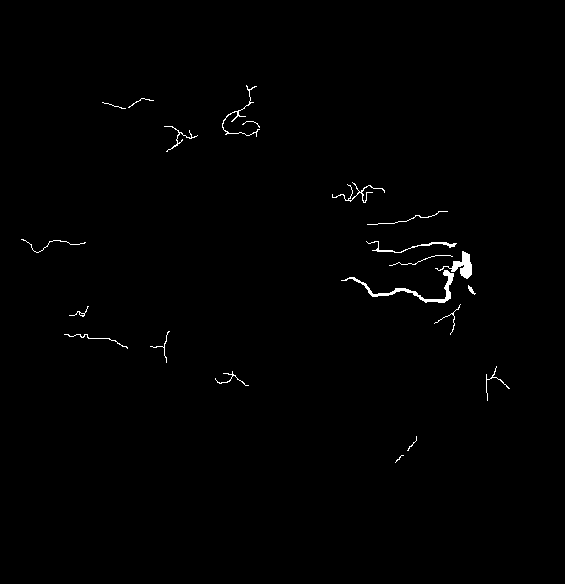

The visual differentiation between arteries and veins can be difficult in some cases, like small vessels with poor contrast and not clearly connected to a specific arterial or venular tree. These cases can be identified with certainty as vessels, but their classification into arteries and veins is uncertain, even for an expert. Additionally, it is common to find crossings between arteries and veins in the retina. Thus, although for these positions either the artery or the vein is above the other, these pixels can be regarded as simultaneously belonging to both types of vessels. This allows to account for continuous arterial and venular trees regardless of crossings below the other one. The identification of these two special situations (uncertain vessels, and vessel crossings) is common in manually annotated retinal vessel classification datasets [38, 42, 43, 44]. Figure 1 shows an example of a ground truth image from the RITE dataset labelled this way, along with its decomposition into arteries, veins, crossings and uncertain vessels.

In order to train the networks following the traditional and MS approaches, the ground truth images from the RITE dataset are adapted, in each case, to the output of the network. In the traditional approach, each pixel of the ground truth is assigned to either background, artery, vein or “uncertain or crossing” class, which comprises both uncertain vessels and crossings. The resulting ground truth is a grayscale image in which each pixel has a numeric label of the class to which it belongs. On the other hand, in the MS approach, each pixel is assigned to any number of the following classes: artery, vein and vessel. In this case, crossings belong to the three classes, and uncertain vessels belong only to the “vessel” class. Background pixels are not assigned to any class. The resulting ground truth is an RGB image in which each channel contains a manual segmentation mask of one of the aforementioned structures. An example of a RITE ground truth adapted to both the traditional and the MS approaches can be found in Figure 7.